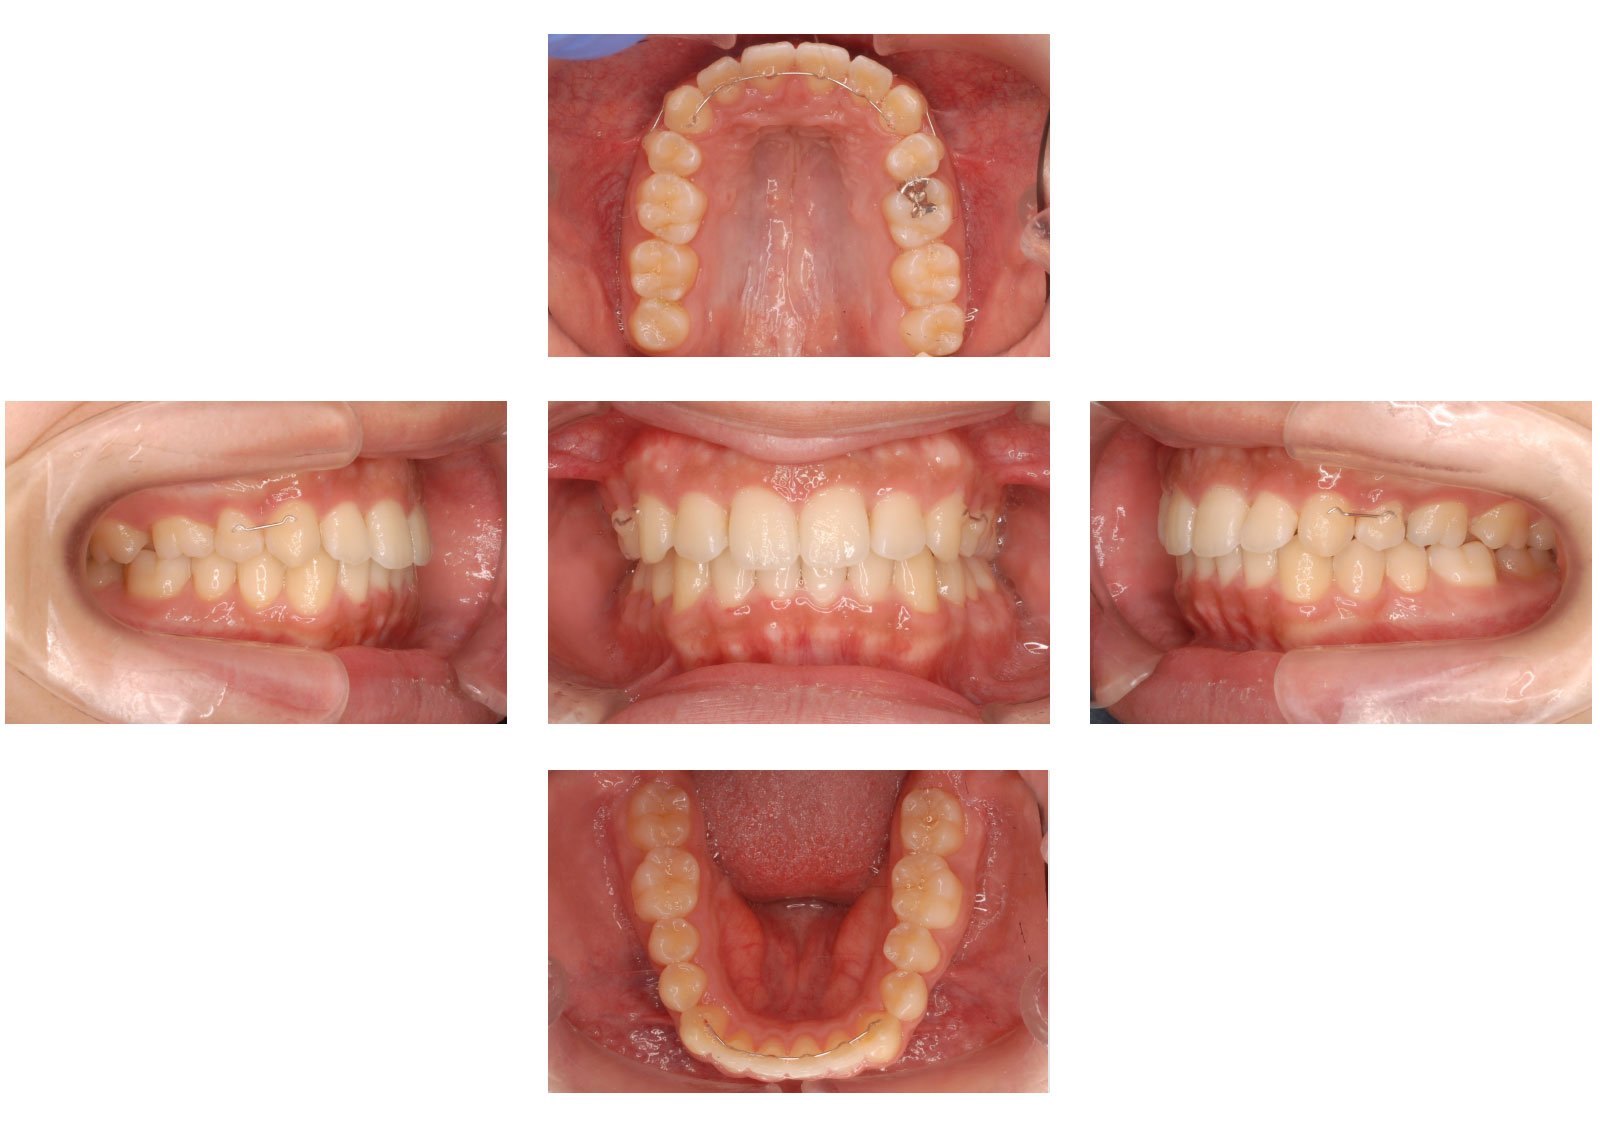

方針 上の前歯が出ているために普段から口が閉じれない状態でした。 上の歯が下の歯よりも歯1本分前に出ていたため、上の左右の歯を抜歯し、上の前歯を後方に下げることできちんとかみ合い、口も閉じやすくすることができました。

リスク 歯科矯正用アンカースクリューが外れたりした場合には、上の前歯が十分に下がらないことがあり、代わりとなる矯正装置が必要となることがあります。